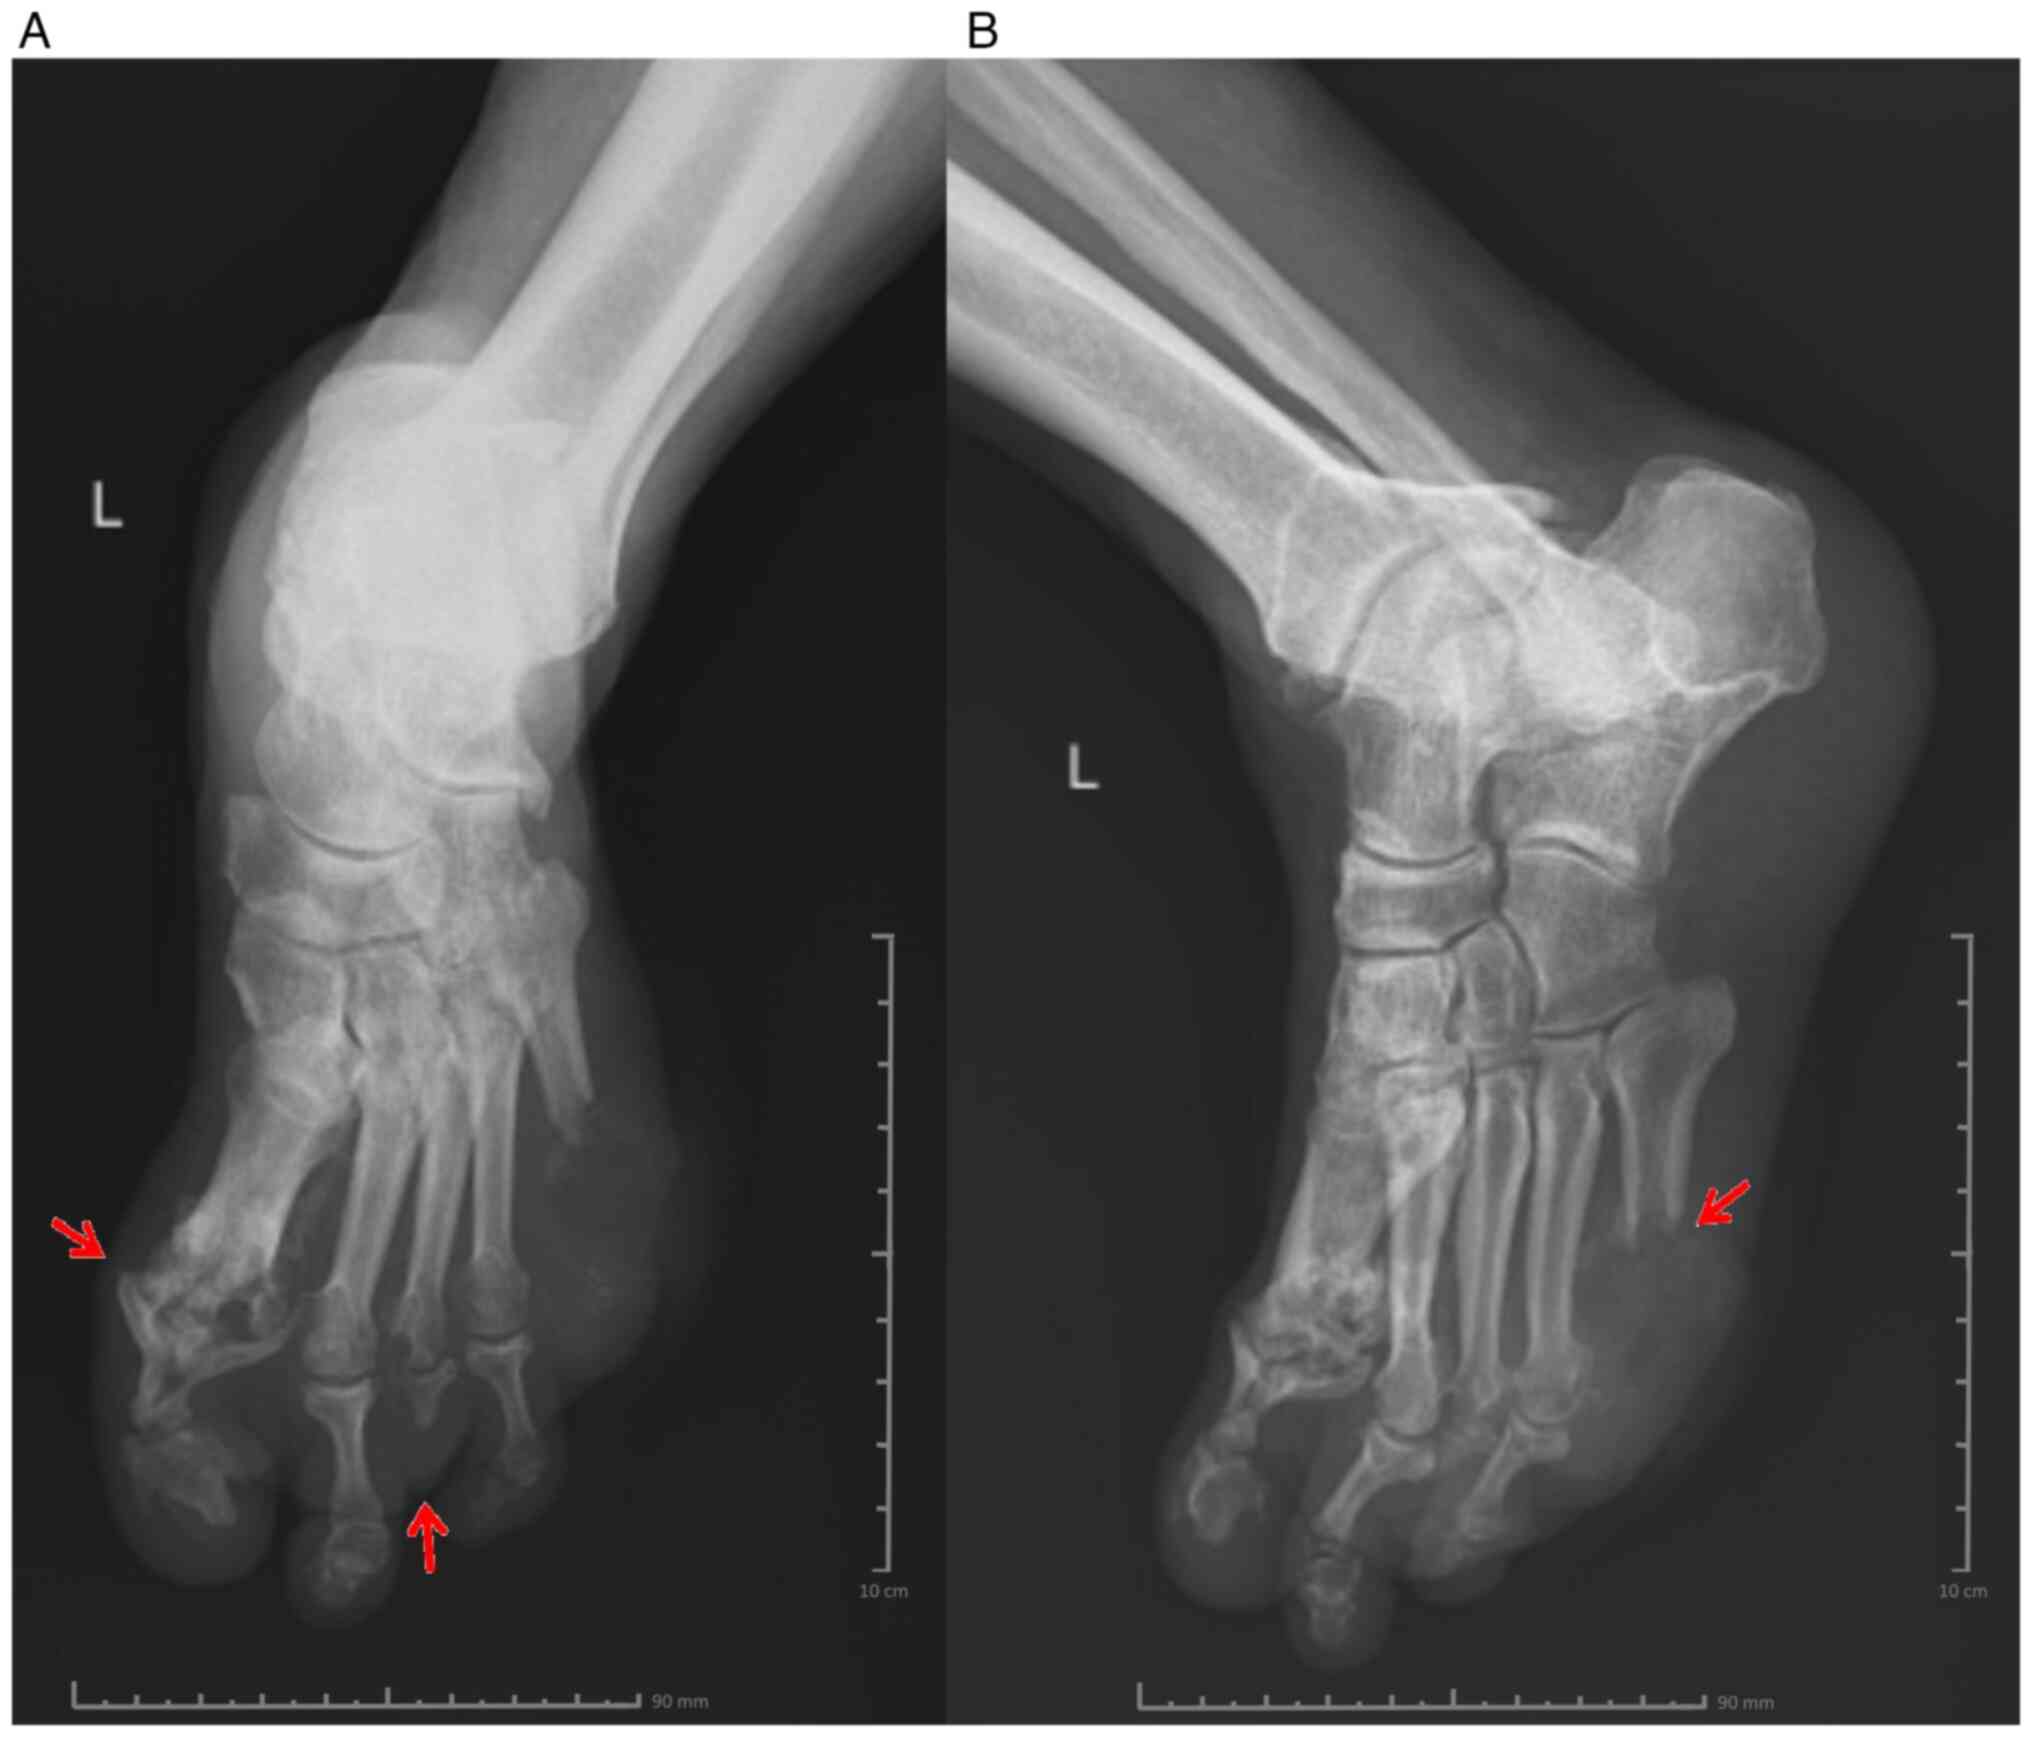

Following the clinical evaluation, a rheumatological consultation was requested, and according to the recommendations, treatment with methylprednisolone was initiated. Oral tablets at 24, 16, 8 and 4 mg concentrations were administered for 7 days each, thus lowering the dose gradually to avoid possible adverse effects, such as increased blood pressure, fluid retention and changes in glucose tolerance. Regarding anti-diabetic therapy, given the high value of the HbA1c and the glycaemic profile of the patient, insulin therapy was initiated, using a basal bolus insulin regimen, in doses that were adjusted daily according to the capillary blood glucose levels of the patient determined 4-7 times/day. Considering the treatment with methylprednisolone and the impact on the carbohydrate metabolism, the patient required increased doses of insulin. The surgical consultation established the need for excisional debridement and amputation of the distal extremity in the left fifth metatarsal, with a tissue sample saved for the antibiogram. The culture revealed methicillin-resistant Staphylococcus aureus (MRSA), and according to the antibiogram (Table III), the patient received antibiotic treatment with a ciprofloxacin intravenous infusion (10 mg/ml, 100 ml) twice a day for 14 days and then ciprofloxacin tablets (500 mg) twice a day for 5 days. X-ray of the left leg (frontal and lateral view) showed changes in the bone structure at the level of the fifth metatarsal, and circumscribed osteolysis at the level of the first metatarsophalangeal joint and the distal extremity of the third metatarsal (Fig. 2A and B).

Figure 2

X-ray of the left leg. X-ray of the left leg showed changes in the bone structure at the level of the fifth metatarsal and circumscribed osteolysis at the level of the first metatarsophalangeal joint and the distal extremity of the third metatarsal. (A) Anterior view and (B) lateral view.